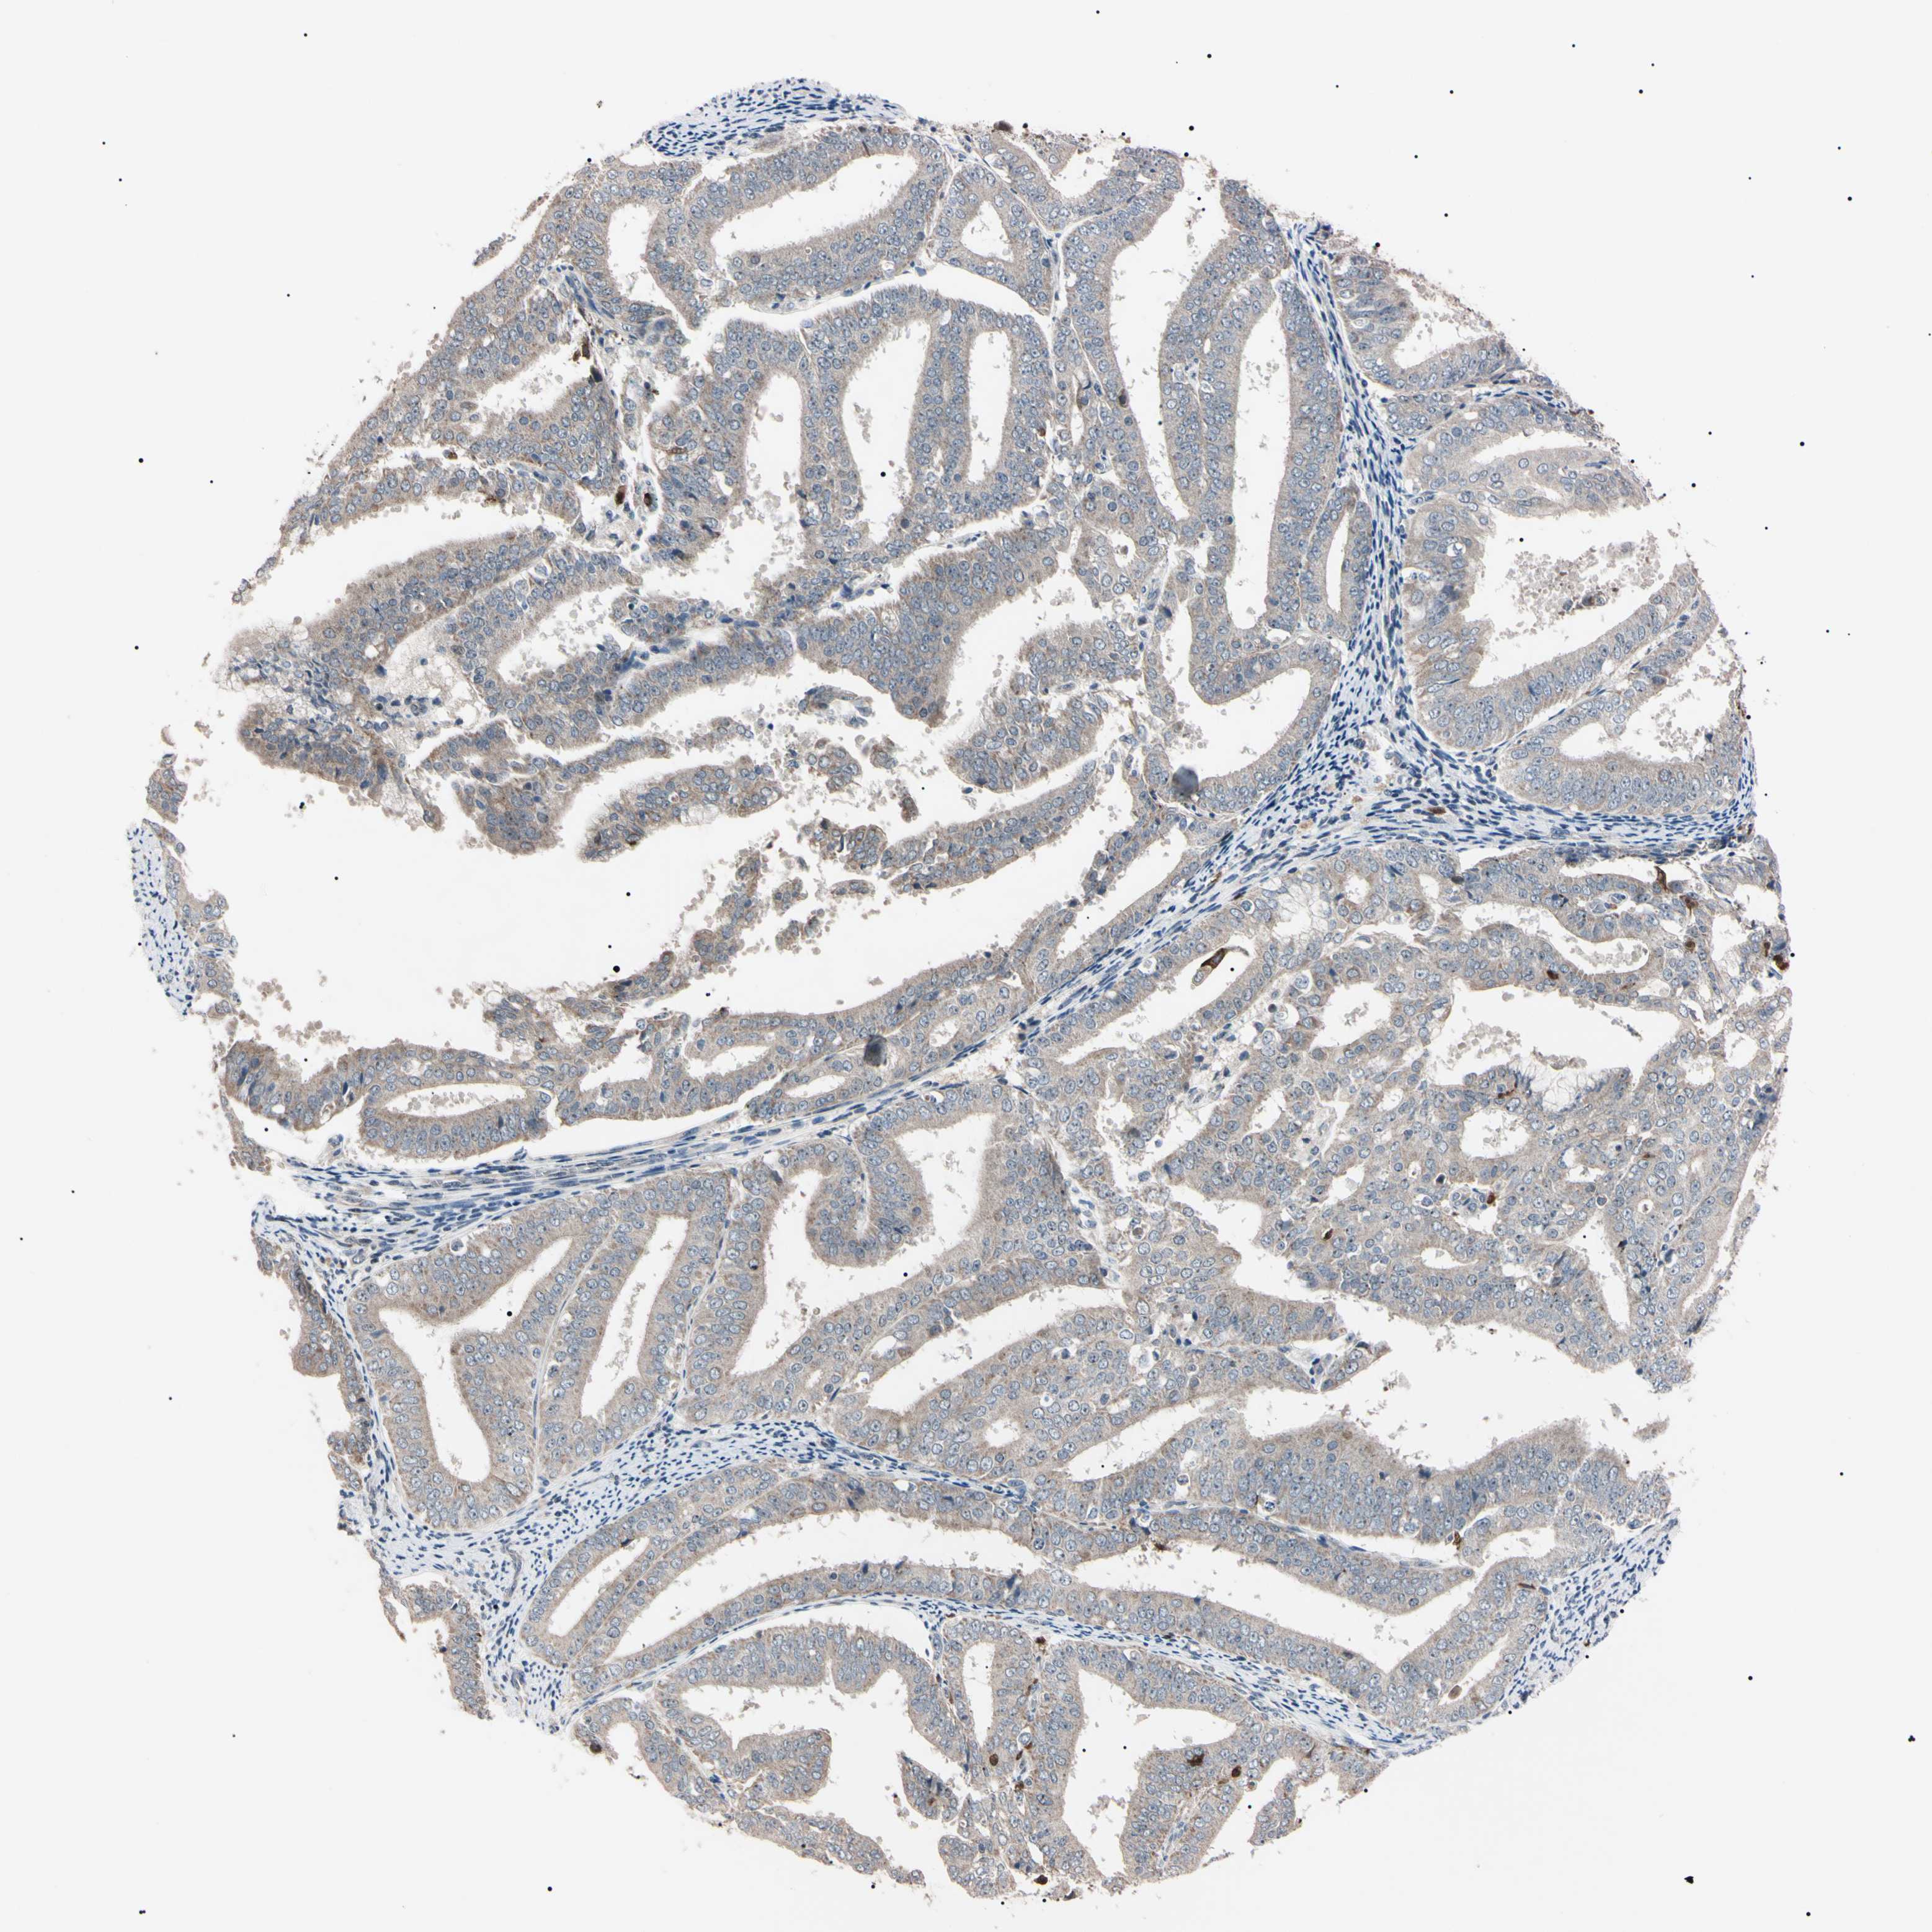

ENDOMETRIAL CANCER - Protein expressioni

A mouse-over function shows sample information and annotation data. Click on an image to view it in a full screen mode. Samples can be filtered based on level of antibody staining by selecting one or several of the following categories: high, medium, low and not detected. The assay and annotation is described here.

Note that samples used for immunohistochemistry by the Human Protein Atlas do not correspond to samples in the TCGA dataset.

Antibody stainingi

Antibody staining in the annotated cell types in the current human tissue is reported as not detected, low, medium, or high, based on conventional immunohistochemistry profiling in selected tissues. This score is based on the combination of the staining intensity and fraction of stained cells.

Each image is clickable and will lead to virtual microscopy that enables deeper exploration of all samples and also displays staining intensity scores, fraction scores and subcellular localization as well as patient and tissue information for each sample.

Antibody HPA008052

Antibody CAB010277

Staining

High

Medium

Low

Not detected

Intensity

Strong

Moderate

Weak

Negative

Quantity

>75%

75%-25%

<25%

None

Location

Nuclear

Cytoplasmic/membranous

Cytoplasmic/membranous,nuclear

Adenocarcinoma, NOS